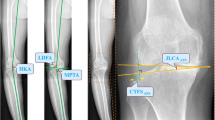

Data of 40 patients with 49 cruciate retaining (CR) TKA who underwent stress radiographs as part of the diagnostic algorithm in a painful knee clinic were prospectively collected. Anterior and posterior stress radiographs were done in 90° and 15° flexion, varus-valgus stress radiographs in 0° and 30° knee flexion. Knee laxity was measured in mm and degrees by two independent observers using standardized landmarks. Intra- and inter-observer single measure intraclass correlations were between 0.92 to 1 and 0.89 to 1, respectively. For evaluation and investigation of the potential cut-off values, two groups of patients with and without revision surgery due to instability were compared. Radiographic measures of standardized z values according to the group without revision due to instability were used to calculate average and maximum laxity z-scores.

Knees undergoing revision TKA due to instability showed significantly (p < 0.001) lower (KSS) pain/function scores (94 ± 6.3, range 80–100; control group: 112 ± 19.2, range 80–148) and total KSS scores when compared to the control group. The laxity values of patients with instability were significantly higher in terms of mean values (p < 0.01) when compared to the control group. The maximum laxity z-score showed the strongest difference between the groups (R2 = 0.26, p < 0.001). The following cut-off values indicating need of revision due to instability were established: in 90° (15°) flexion—anterior translation 5.2 mm (22.4 mm), posterior translation 16.6 mm (13.2 mm); varus stress in 0° (20°–30°) flexion—inlay gap 5.2 mm (6.1 mm) or joint angle 6.1° (6.8°); valgus stress in 0° (20°–30°) flexion—inlay gap 4.6 mm (5.7 mm) or joint angle 5.2° (7.1°).